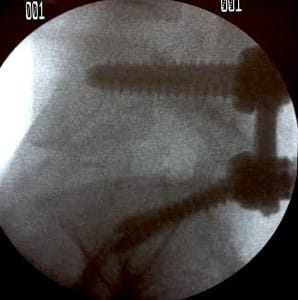

La técnica percutánea con tornillos transpediculares y barras es la máxima expresión de la cirugía de columna de mínima invasión. A diferencia del método clásico, donde se realizaba una incisión extensa y se separaban los músculos de la columna, el abordaje percutáneo utiliza pequeñas incisiones en la piel (de apenas un par de centímetros). A través de estas aperturas, y con la guía de equipos de rayos X de alta precisión, el cirujano coloca los tornillos y las barras que darán estabilidad a la columna.

Los tornillos transpediculares actúan como «anclajes» dentro del cuerpo vertebral, mientras que las barras funcionan como puentes que conectan estos anclajes. Juntos, forman un armazón interno que mantiene la columna en la posición correcta mientras el hueso se fusiona de manera natural. Al realizarse de forma percutánea, el cirujano desliza las barras por debajo de la piel y los músculos, evitando el trauma innecesario a los tejidos blandos que rodean la columna.

Dato Clave: La precisión es fundamental en este procedimiento. El uso de monitoreo neurofisiológico y navegación intraoperatoria permite al cirujano colocar los implantes con un margen de error milimétrico, garantizando la seguridad de las raíces nerviosas.